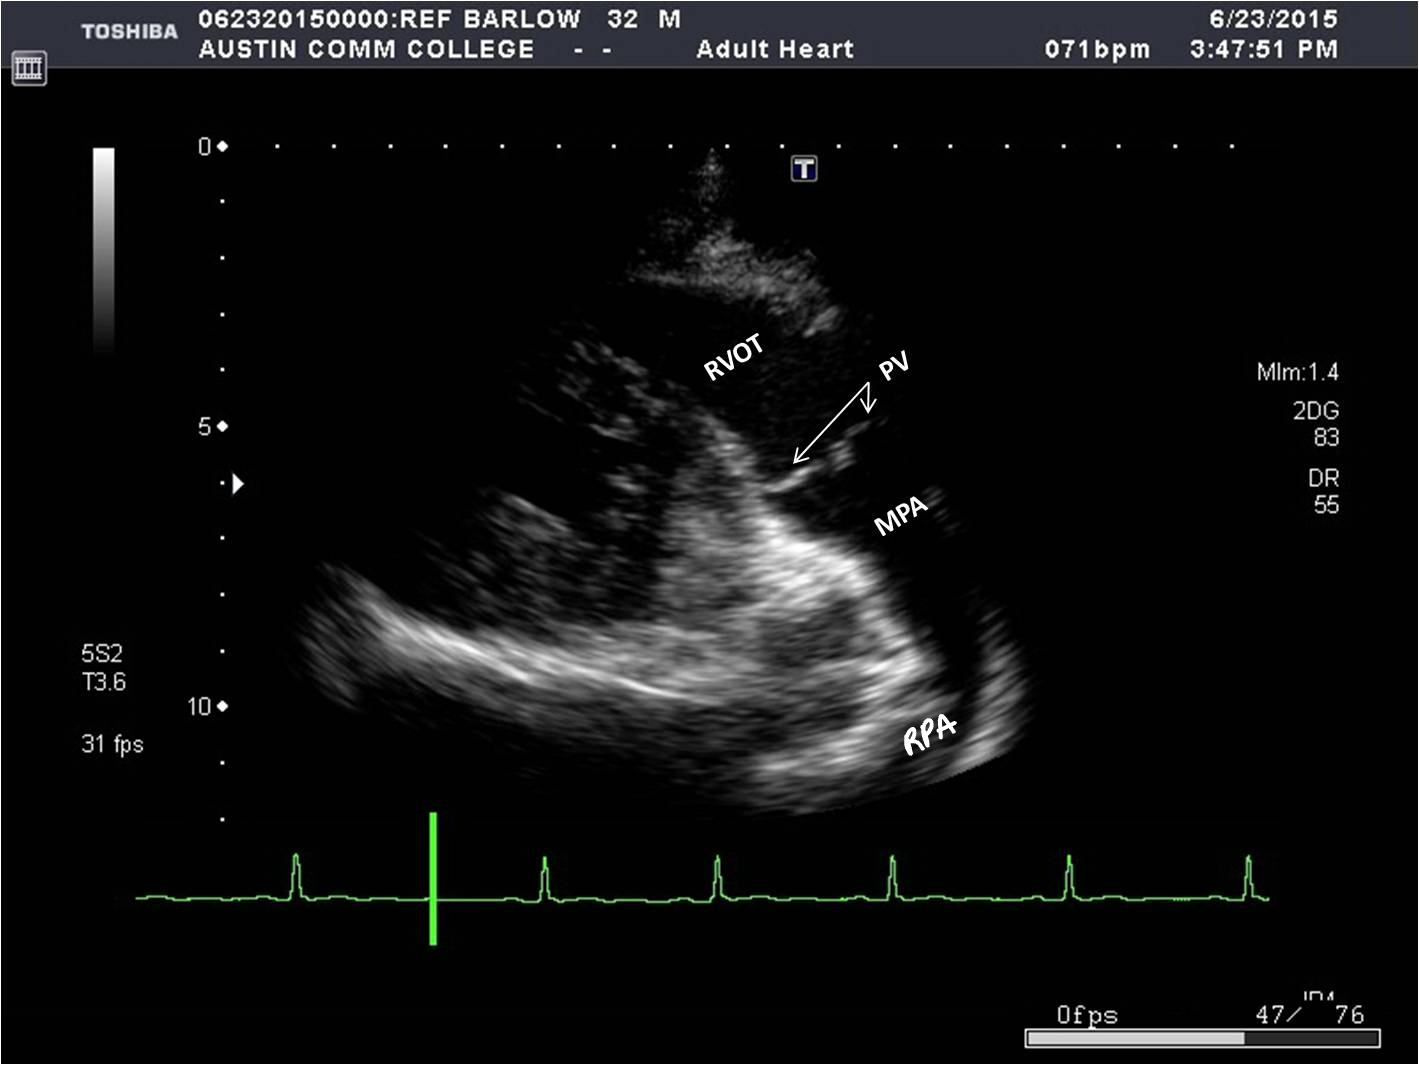

How do you get to a parasternal long axis right ventricle outflow tract (LAX RVOT) from parasternal LAX view?

By angling the transducer towards the patient’s left shoulder.

What structures can be seen in a parasternal LAX RVOT?

* RVOT

* PV

* Main pulmonary artery (MPA)

* Right pulmonary artery (RPA)

* PV

* Main pulmonary artery (MPA)

* Right pulmonary artery (RPA)

46

What is a good way of remembering whether or not you are looking at parasternal LAX RVIT or RVOT?

If you are IN, you’re HIP, but if you’re OUT, you get the shoulder.